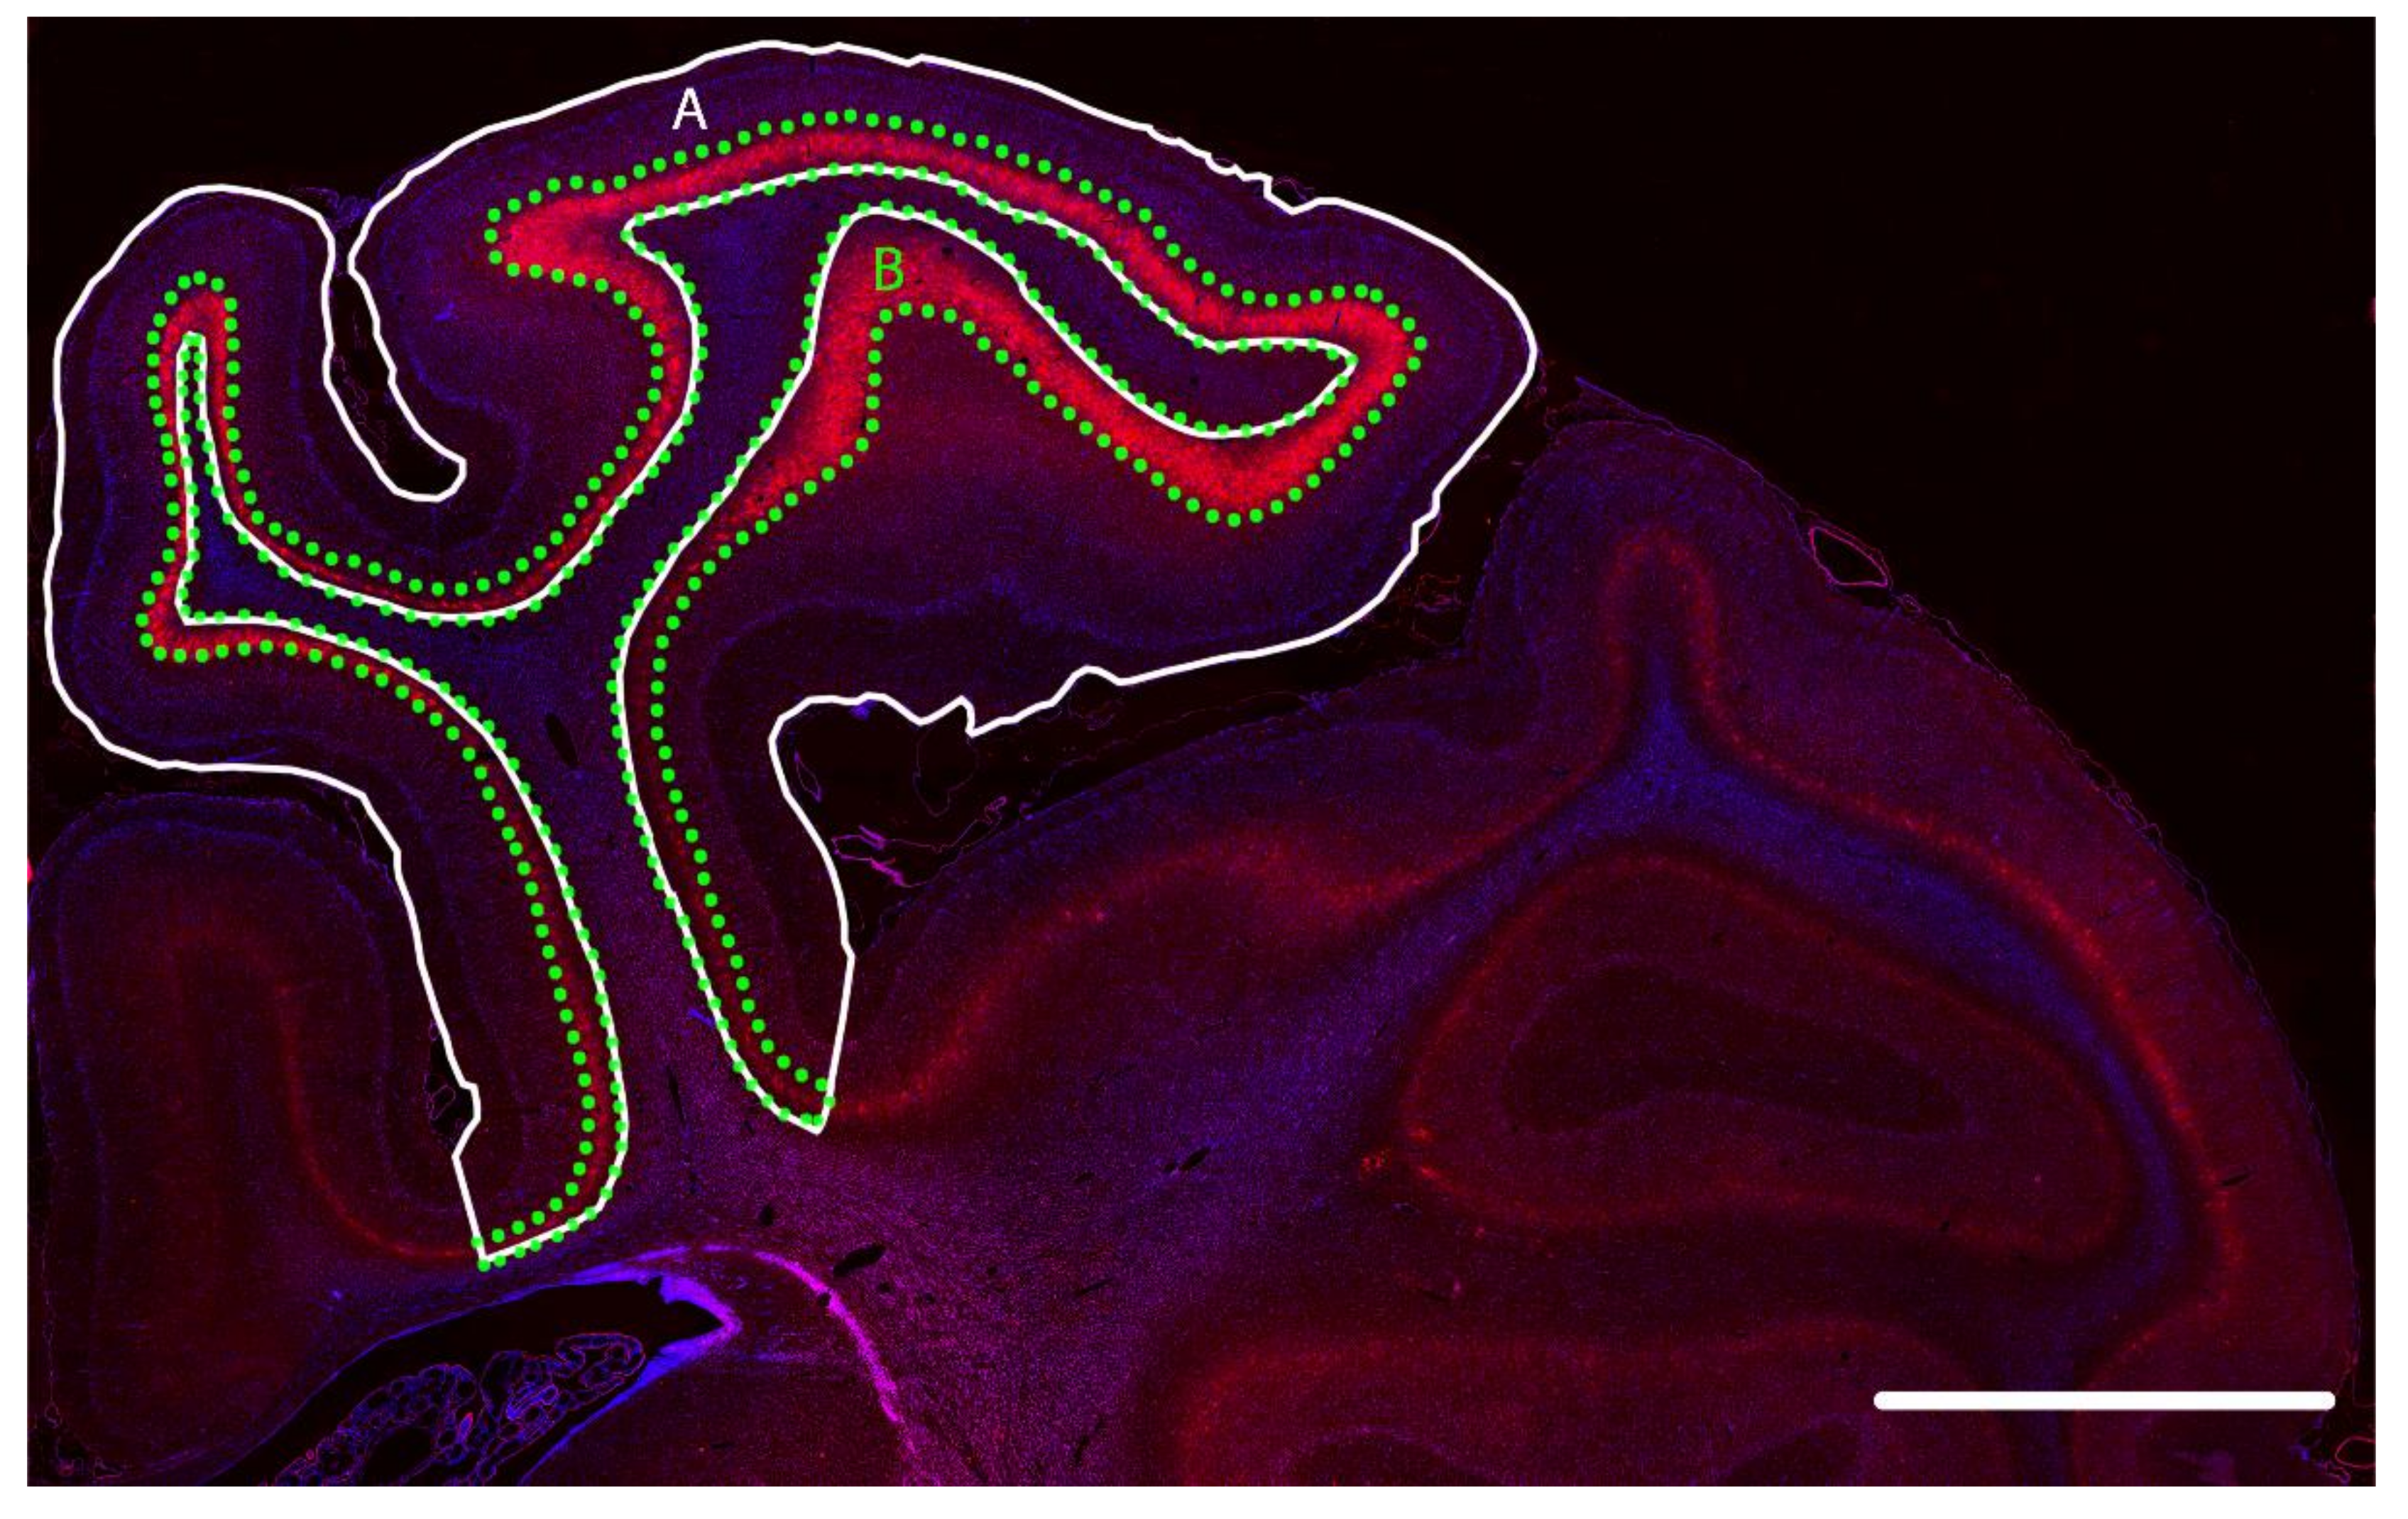

2.1. Survival of GABAergic Interneurons in the Parasagittal Cortex after Cerebral Ischemia

4.6. Image Analysis